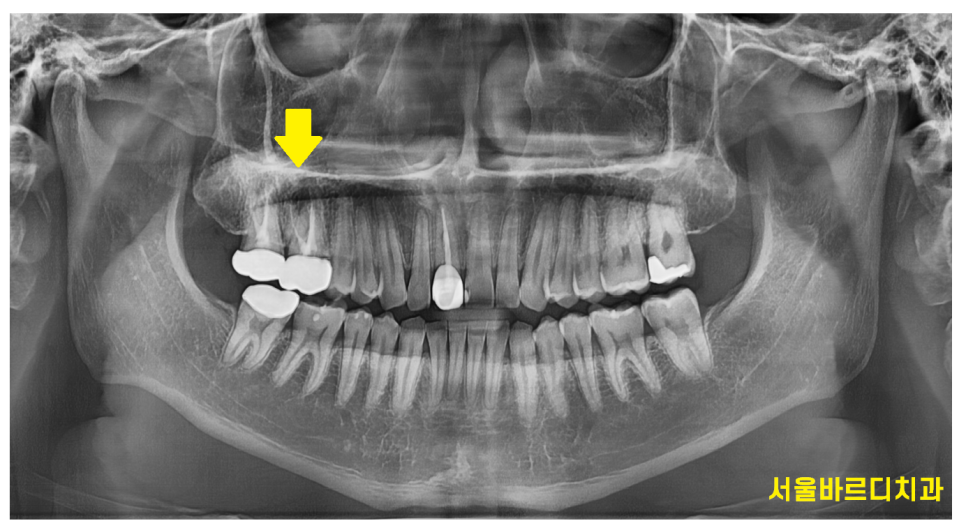

3D ct 등을 통해 정밀한 검사를 진행한 결과,

치아 뿌리 주변의 염증으로 한쪽 뼈를 녹였네요.

ct 상 한쪽 뼈만 녹아있는 상황이라

x-ray를 봐서는

염증이 없어진건지 잘 모르시겠죠~?

변화가 된 모습만 비교해드릴께요~

뿌리 절반 이상 염증들이

3달의 치료과정을 통해

손톱만큼 줄어들었습니다.

이제 뿌리 끝 까만 부분

거의 보이지 않습니다.

염증이 남아있으면 제대로 뼈가 차지 않는대요.

깨끗하게 염증이 없어졌기 때문에

까맣게 녹아 버린 뼈가

다시 하얗게 채워진 모습을 볼 수있네요~